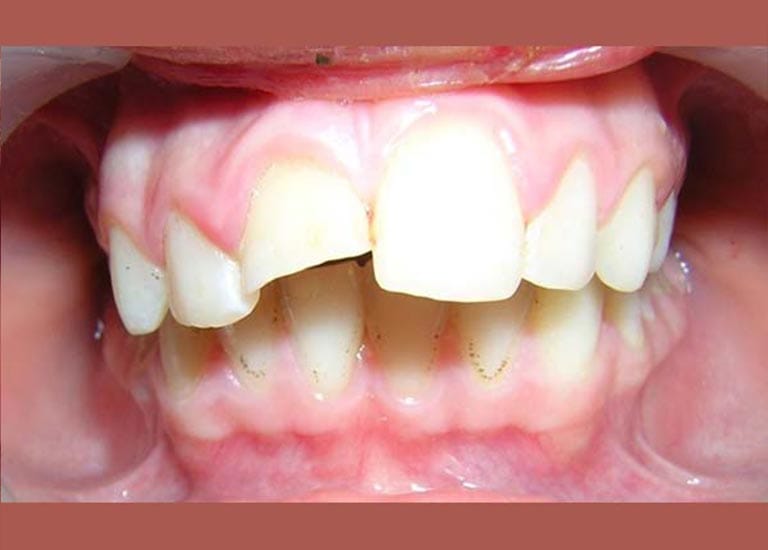

عانت هذه الفتاة الصغيرة من بروز شديد في الأسنان وصل إلى 1 سم، وكان سببه الرئيسي هو تراجع الفك السفلي، وهو ما كان يظهر بوضوح على بروفيل وجهها الجانبي.

كما تظهر الصور، كان التحسن جذرياً ليس فقط في الابتسامة ولكن في تناسق ملامح الوجه بالكامل. تم تصحيح البروز، وتحسنت علاقة الفكين، وحصلت صديقتنا الصغيرة على ابتسامة جميلة وواثقة.